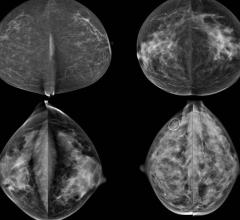

Despite decades of progress in breast imaging, one challenge continues to test even the most skilled radiologists ...

With all the conflicting information surrounding screening mammography, it is hard for breast radiologists not to be just as confused as the patients and referring clinicians. As a breast radiologist, I am passionate about breast imaging and the patients I serve.